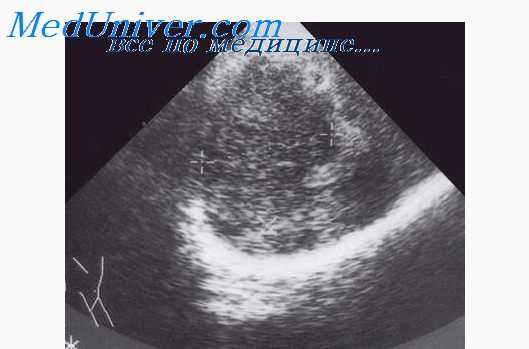

Ультразвуковые данные:

• Расширение собирательной системы почки.

• Иногда внутренние эхо-сигналы высокой интенсивности, указывающие на гной или детрит.

Точность ультразвуковой диагностики: ультразвуковое исследование позволяет предположить правильный диагноз, для подтверждения которого проводится чрескожная аспирационная биопсия. Ответ на терапевтические мероприятия и последующий ультразвуковой контроль также подтверждают диагноз.